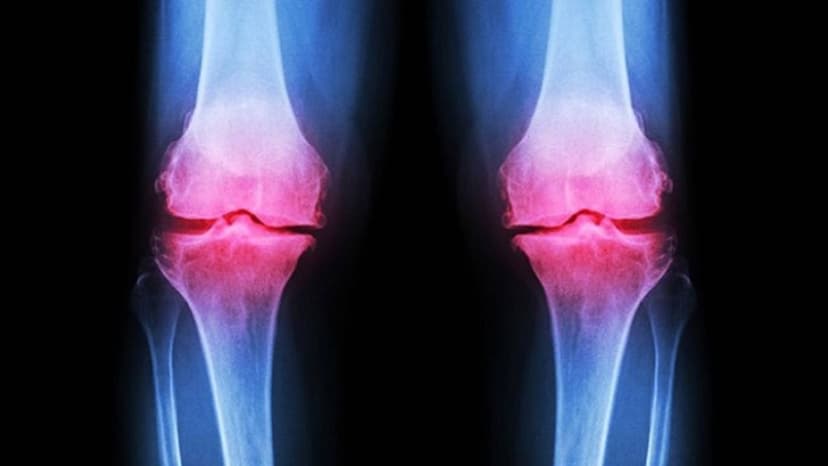

Thoái hóa khớp gối là tình trạng tổn thương phần sụn khớp đi kèm với phản ứng viêm và giảm thiểu lượng dịch khớp do quá trình tái tạo sụn khớp không kịp bù vào lớp sụn đã mất theo thời gian.

Bệnh lý thoái hóa khớp gối gây đau kéo dài, làm biến dạng khớp gối cũng như suy giảm chức năng sinh hoạt hàng ngày và gây ảnh hưởng tới chất lượng cuộc sống. Nếu không điều trị dứt điểm thì thoái hóa khớp gối có khả năng gây teo cơ, mất khả năng vận động thậm chí là tàn phế.

Bệnh lý thoái hóa khớp gối gây đau kéo dài và làm biến dạng khớp gối cũng như suy giảm chức năng sinh hoạt hàng ngày